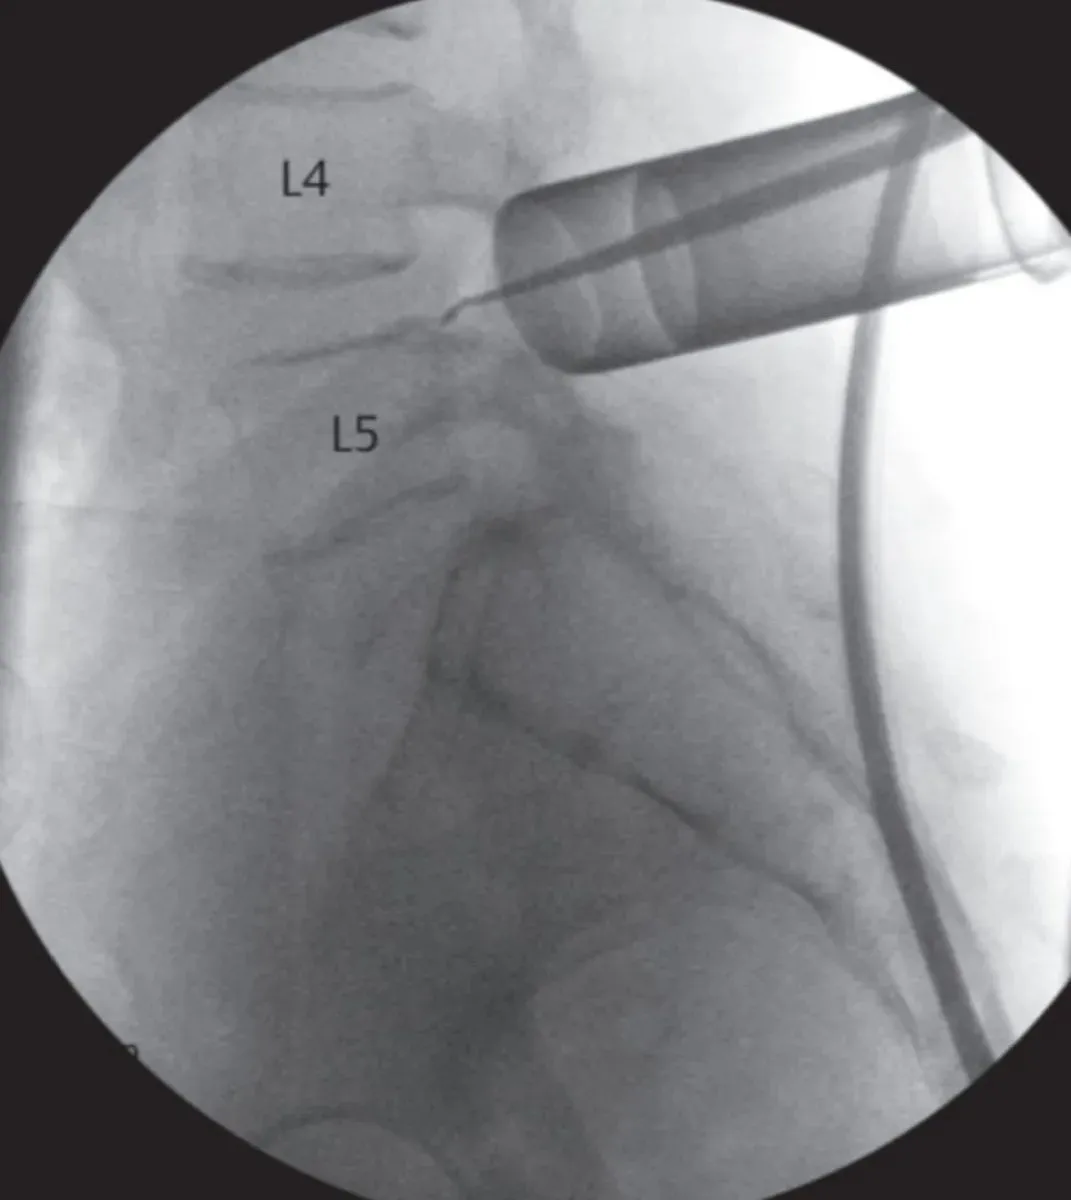

Desde salud remarcaron que se fueron incorporando prácticas quirúrgicas de alta complejidad y mínima invasión en el tratamiento de patologías de columna vertebral. Además de las técnicas quirúrgicas convencionales que siempre se realizaron en el hospital para el tratamiento de fracturas, tumores y enfermedades degenerativas, desde hace más de un año se han incorporado intervenciones mediante técnicas mínimamente invasivas (MISS, por sus siglas en inglés: Minimally Invasive Spine Surgery).

Estas técnicas, que se realizan a través de sistemas tubulares, representan un gran avance en el abordaje de patologías como hernias de disco, artrosis, compresiones medulares y radiculares, así como en el tratamiento de diferentes tipos de tumores, tanto benignos como malignos. Entre sus ventajas, se destacan la menor lesión de tejidos blandos, una reducción significativa del sangrado y del dolor postoperatorio, menor riesgo de infecciones y una recuperación más temprana.